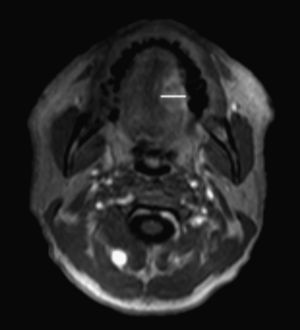

En el estudio preoperatorio se realizó el estudio radiológico de la tumoración por RM en nuestro centro, con el mismo equipo, tras la administración de contraste con gadolinio, y se objetivó la medida del espesor tumoral. En nuestro centro la resonancia de cabeza y cuello se realiza en un equipo PHILIPS INTERA 1,5 T. Las secuencias básicas que se emplean en los estudios ante una sospecha diagnóstica de cáncer de lengua son: T1 turbo spin echo (TSE) como estudio basal para valorar la anatomía y previo a la inyección de contraste, short T1 inversion recovery (STIR) y estudio dinámico sobre T1 con supresión de grasa en la fase arterial, capilar y tardía. Se inyectan 10ml de gadolinio (GADOVIST® de BAYER) a velocidad de 2ml/s con lavado posterior de suero. El empleo de gadolinio de forma rutinaria es fundamental para conseguir una correcta definición del tumor y poder valorar extensión perineural.

La cuantificación del tamaño tumoral se realiza en la secuencia dinámica, ya que es la que mejor define el margen tumoral al aumentar la señal de este tras la administración de gadolinio. Se obtiene la medición en el plano axial y coronal (fig. 1).

Radiológicamente la medida del espesor corresponde a la medida de mayor dimensión perpendicular a la tangente del margen mucoso (existente o figurado) en el punto de mayor infiltración.